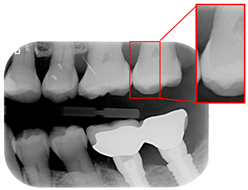

Caries are a prevalent issue in dental healthcare, affecting nearly all adults and 60–90% of children, posing a significant public health challenge, especially with dental braces or dental restorations [,]. Traditional dental examinations relying on visual inspection or radiographic images [,] can be subjective and time-consuming. Related studies have utilized auxiliary software for oral examinations, such as methods of geometric alignment to compare noise levels in subtraction images [], jawbone regeneration [], and corticalization measurement []. With the rise of AI, automated caries detection using image processing and deep learning technologies has gained increasing attention []. Deep learning techniques such as convolutional neural networks (CNNs) have shown significant performance in medical image classification by leveraging large-scale annotated datasets [,]. In dentistry, CNNs have been applied to detect apical lesions, offering objective interpretation and reducing diagnostic time []. Bitewing radiographs (BWs) are commonly used to identify caries and periodontal conditions. Tooth region extraction from BWs can be performed using filtering, binarization, and projection methods [,,,]. The YOLO object detection algorithm enables real-time localization with high accuracy and speed [,]. This study uses YOLO to detect caries under restorations and dental braces, as illustrated in Figure 1.

Figure 1.

BW images with disease. (a) Dental braces. (b) The red circle represents the restoration. (c) The gap in the red circle indicates dental caries under the restoration.